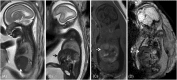

Human cytomegalovirus (CMV) is an ubiquitous pathogen, with a high worldwide seroprevalence. When acquired in the prenatal period, congenital CMV (cCMV) is a major cause of neurodevelopmental sequelae and hearing loss. cCMV remains an underdiagnosed condition, with no systematic screening implemented in pregnancy or in the postnatal period. Therefore, imaging takes a prominent role in prenatal diagnosis of cCMV. With the prospect of new viable therapies, accurate and timely diagnosis becomes paramount, as well as identification of fetuses at risk for neurodevelopmental sequelae. Fetal magnetic resonance imaging (MRI) provides a complementary method to ultrasound (US) in fetal brain and body imaging. Anterior temporal lobe lesions are the most specific finding, and MRI is superior to US in their detection. Other findings such as ventriculomegaly, cortical malformations and calcifications, as well as hepatosplenomegaly, liver signal changes and abnormal effusions are unspecific. However, when seen in combination these should raise the suspicion of fetal infection, highlighting the need for a full fetal assessment. Still, some fetuses deemed normal on prenatal imaging are symptomatic at birth or develop delayed cCMV-associated symptoms, leaving room for improvement of diagnostic tools. Advanced MR sequences may help in this field and in determining prognosis, but further studies are needed.